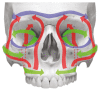

Fractures of the midface pose a serious medical problem as for their complexity, frequency and their socio-economic impact. Interdisciplinary approaches and up-to-date diagnostic and surgical techniques provide favorable results in the majority of cases though. Traffic accidents are the leading cause and male adults in their thirties are affected most often. Treatment algorithms for nasal bone fractures, maxillary and zygomatic fractures are widely agreed upon whereas trauma to the frontal sinus and the orbital apex are matter of current debate. Advances in endoscopic surgery and limitations of evidence based gain of knowledge are matters that are focused on in the corresponding chapter. As for the fractures of the frontal sinus a strong tendency towards minimized approaches can be seen. Obliteration and cranialization seem to decrease in numbers. Some critical remarks in terms of high dose methylprednisolone therapy for traumatic optic nerve injury seem to be appropriate. Intraoperative cone beam radiographs and preshaped titanium mesh implants for orbital reconstruction are new techniques and essential aspects in midface traumatology. Fractures of the anterior skull base with cerebrospinal fluid leaks show very promising results in endonasal endoscopic repair.